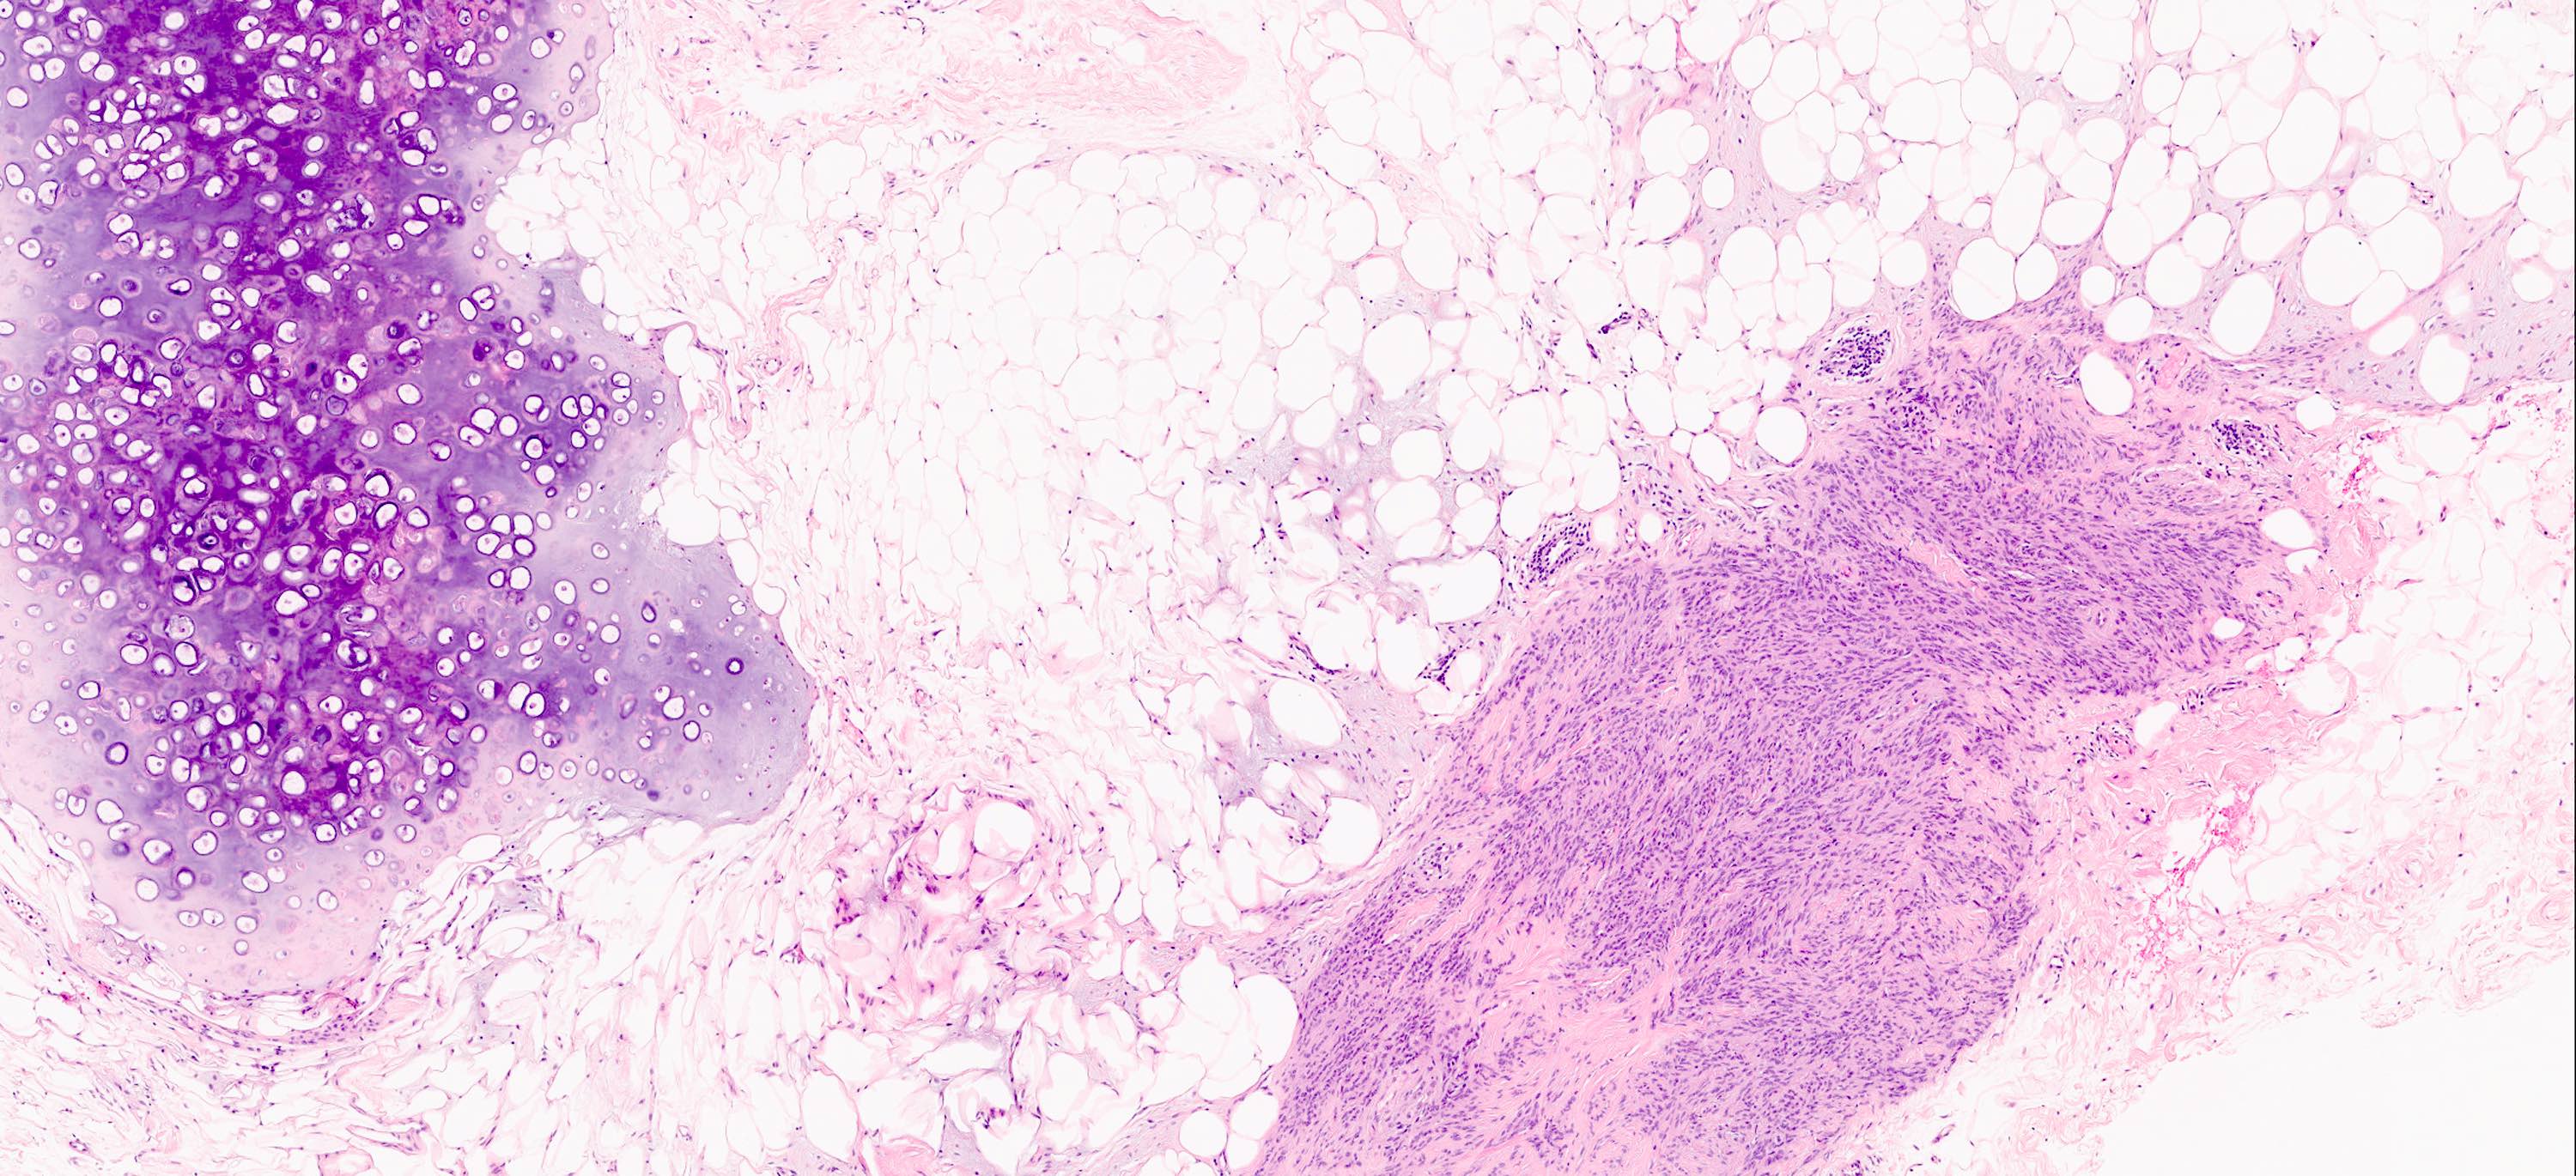

Microscopic (histologic) description

- Well circumscribed, lacks true capsule, rarely infiltrative

- Bland, uniform, short to elongated spindle cells arranged as short haphazard intersecting fascicles admixed with bands of hyalinized, brightly eosinophilic collagen and variable amounts of fat

- No more than mild nuclear atypia

- Mitoses usually absent, atypical mitoses and necrosis absent

- Mast cells common, perivascular lymphocytic infiltrates on occasion

- Focal myxoid stromal changes common

- May show smooth muscle leiomyomatous differentiation (elongated spindle cells with cigar shaped nuclei and pink cytoplasm)

- Rarely cartilaginous or osseous components

- Variants:

- Collagenized / fibrous: collagenous stroma predominates, may have hypocellular myofibroblastic spindle cell component

- Cellular: dense proliferation of myofibroblasts, ratio of spindle cells to collagen increased compared with classical variant, may have infiltrative borders, storiform or herringbone arrangement

- Infiltrative: irregular margins, grows into surrounding mammary parenchyma entrapping glandular tissue

- Myxoid: stellate and spindle cells in abundant myxoid stroma (Histol Histopathol 2016;31:1)

- Deciduoid: large round, polygonal cells with abundant eosinophilic glassy cytoplasm, single or multiple prominent nucleoli which may be eccentrically placed, binucleation, sharp cell borders, eosinophilic intracytoplasmic inclusions (Histopathology 2008;52:652)

- Lipomatous: abundant adipocytic component

- Epithelioid: oval to polygonal cells arranged in clusters, cords, alveolar groups, linear strands, mono, bi or multinucleated, may have eccentrically placed nuclei with small nucleoli, well defined cell borders, single file arrangement may mimic invasive lobular carcinoma (Am J Surg Pathol 2009;33:1085)

- Atypical: single or scattered atypical mono or multinucleated cells with mild to severe nuclear pleomorphism, regarded as degenerative (Arch Pathol Lab Med 2008;132:1813)

Microscopic (histologic) images